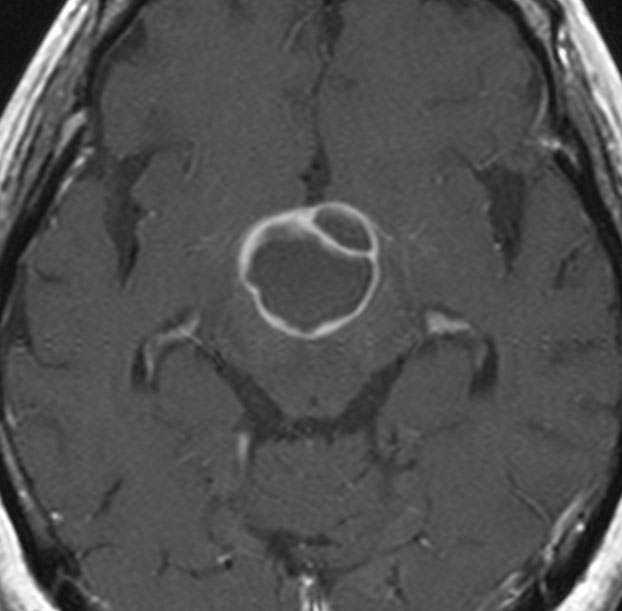

成人の第3脳室内部に局在する頭蓋咽頭腫です。経脳梁法で両側のモンロー孔から全摘出しました。下垂体組織は残っています。これは乳頭状頭蓋咽頭腫と呼ばれるもので,成人にしか発生しません,のう胞がなく石灰化もないのが大きな特徴です。境界が明瞭で柔らかく摘出が簡単なタイプとして知られています。この患者さんも術後に下垂体機能不全も視床下部障害も生じませんでした。

第3脳室内のadamantinomatous craniopharyngiomaです。これを両側前頭開頭,経脳梁法 transcallosall approachで摘出しました。下垂体と下垂体柄を温存するためです。

初回手術から6年後,原発部位に腫瘍はありません。しかし,前頭部大脳鎌(赤矢印)に腫瘍が発生しました。これは手術経路(緑の線)に沿った位置にあるので,drop metastasisだとわかりました。病理は初回と同じものです。このdrop metastasisは意外に多いものです。頭蓋咽頭腫は,極小の腫瘍片でも脳表や脳槽にこぼれ落ちれば,そこで着床して,数年後に再発となって現れるということを示しています。ですから,手術の時に断片を残したり落としたりしてはなりません。